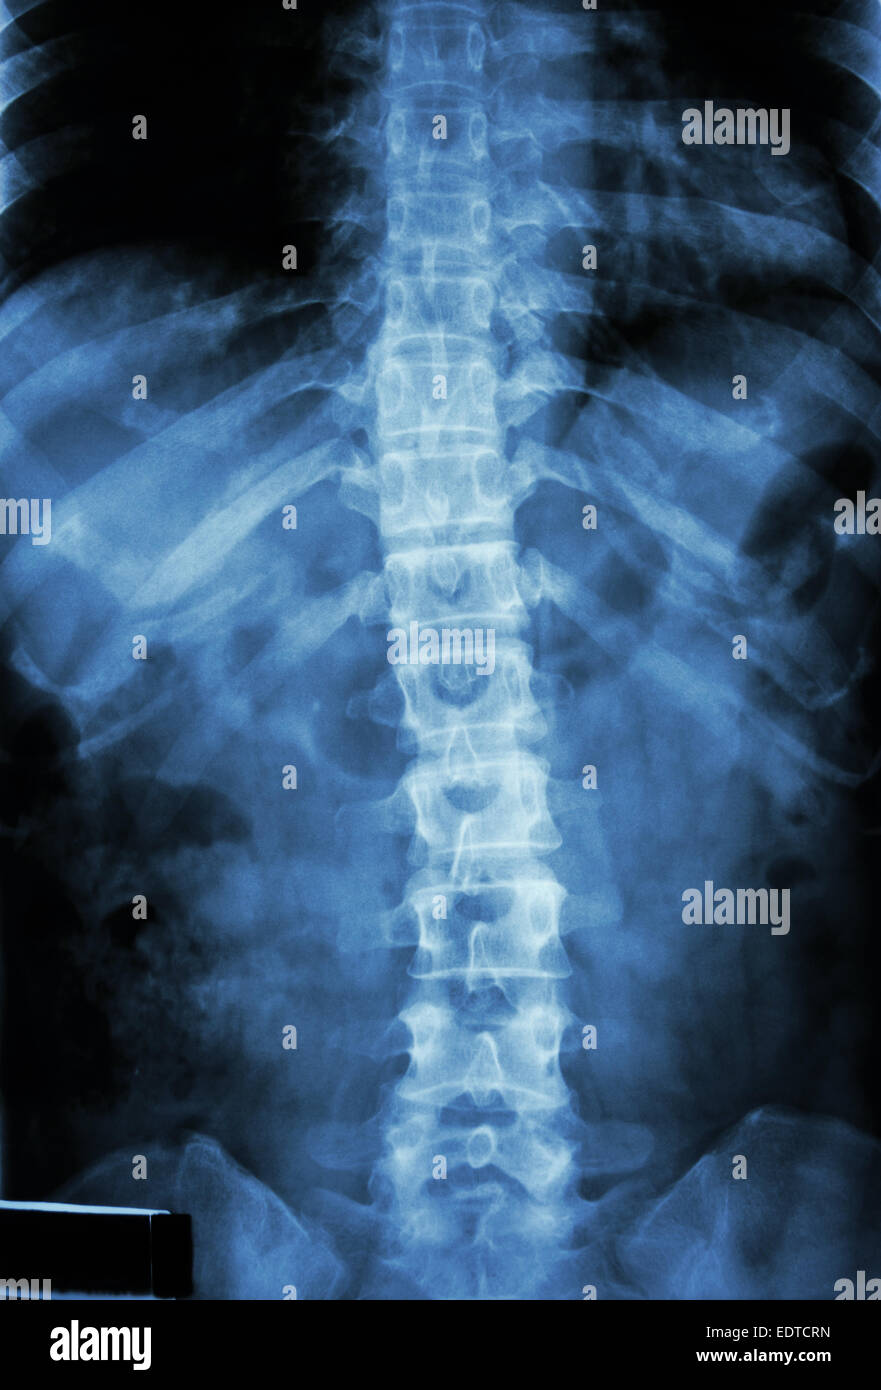

Xray of the lumbosacral spine. Normal. Perfect. Stock Photo Adobe Stock What Does A Normal Lumbar X-Ray Look Like This article lists examples of normal imaging of the spine and surrounding structures, divided by region and modality. This area includes the lumbar region and the sacrum, the area that connects the spine to the pelvis. Your sacrum consists of five small, fused. Example of a normal lumbar spine. This article lists examples of normal imaging of the spine and. What Does A Normal Lumbar X-Ray Look Like.

Xray of normal human lumbar spine (lower back) Stock Image P116/0206 What Does A Normal Lumbar X-Ray Look Like This article lists examples of normal imaging of the spine and surrounding structures, divided by region and modality. These five vertebrae make up your lower back. Your sacrum consists of five small, fused. This area includes the lumbar region and the sacrum, the area that connects the spine to the pelvis. Example of a normal lumbar spine. This article lists. What Does A Normal Lumbar X-Ray Look Like.

Film Xray of Normal Human Lumbar Spine . Stock Image Image of back What Does A Normal Lumbar X-Ray Look Like This area includes the lumbar region and the sacrum, the area that connects the spine to the pelvis. These five vertebrae make up your lower back. This article lists examples of normal imaging of the spine and surrounding structures, divided by region and modality. Your sacrum consists of five small, fused. This article lists examples of normal imaging of the. What Does A Normal Lumbar X-Ray Look Like.